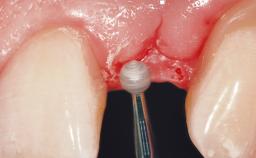

Late Placement of an Implant in a Maxillary Left Central Incisor Site

A 36-year-old female patient was referred for the replacement of the upper left central incisor (tooth 21), which had fractured. Although the tooth had been asymptomatic for many years, the crown began to loosen, at which time she presented to her dentist for an assessment. Teeth 21 and 22 had both been endodontically treated many years previously. She was a healthy individual and a non-smoker.

The crown of tooth 21 was splinted to the adjacent teeth with composite resin, and the gingiva was inflamed.